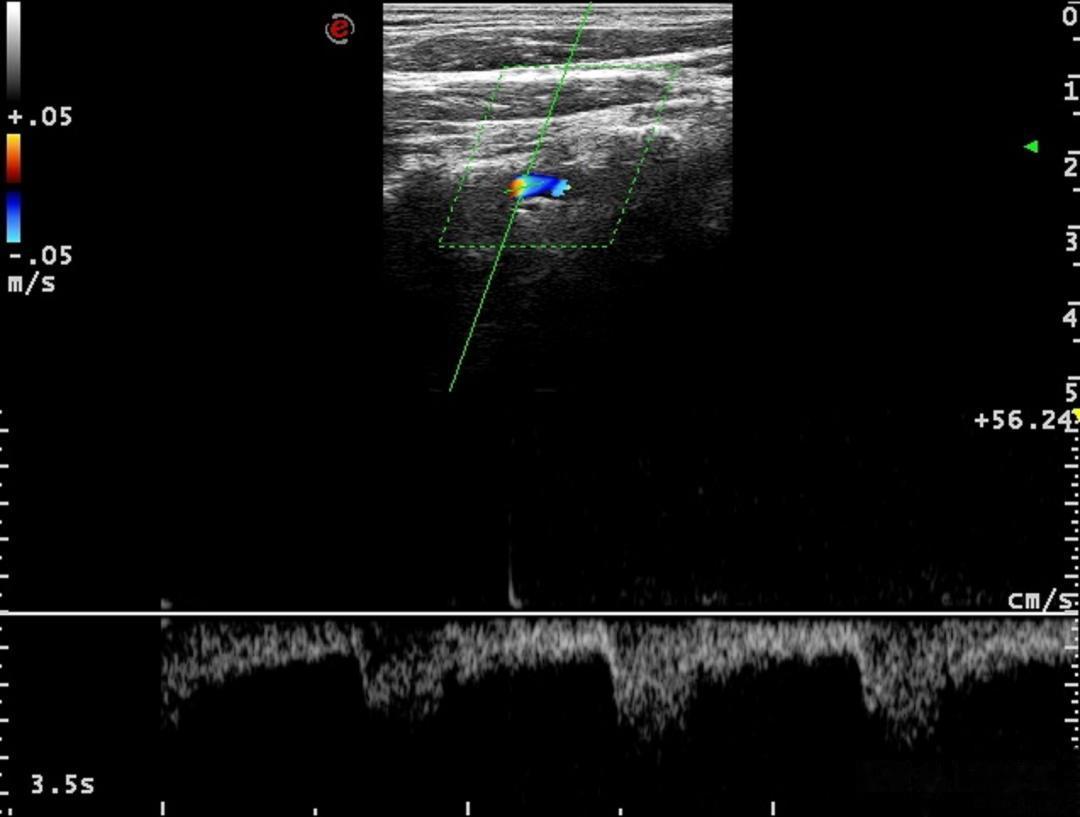

超声诊断科血管疾病超声组陈曦医生通过详细扫查发现,李伯伯右侧锁骨下动脉起始处存在一枚较大斑块,导致血管狭窄率超过50%。同时,其右侧椎动脉起始处存在先天性轻度狭窄,且椎动脉血流方向完全逆转,形成典型的“锁骨下动脉窃血”现象。陈医生解释,由于锁骨下动脉狭窄引发虹吸效应,本应供应脑部的血液逆流至病变血管,导致椎-基底动脉缺血及上肢供血不足,从而引发头晕、视物模糊、上肢乏力等症状。

进一步超声评估显示,李伯伯右侧椎动脉血流频谱在收缩期和舒张期均呈完全反向,确诊为III型完全型窃血。基于这一明确诊断,心血管团队为其实施了锁骨下动脉支架植入术。术后,李伯伯的头晕及上肢无力症状完全消失,血压恢复对称,桡动脉搏动明显增强。医生特别叮嘱他控制运动强度,避免长时间上肢用力,并定期复查血管状况。

锁骨下动脉窃血综合征是一种因动脉狭窄或闭塞导致血流逆流的血管疾病,常见症状包括眩晕、耳鸣、患肢发冷疼痛等,严重时可引发脑梗死。瑞金医院专家指出,彩色多普勒超声是诊断该病的首选方法,可精准定位病变部位、评估狭窄程度,并为后续治疗提供依据。